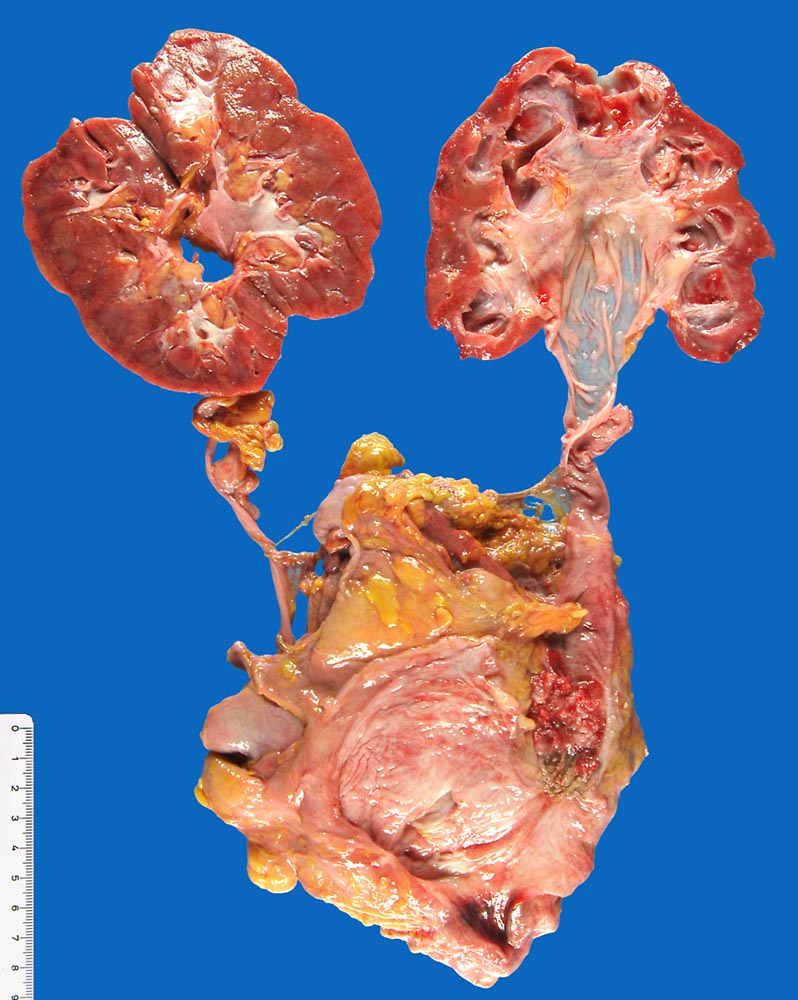

Wenn keine Metastasen vorliegen, kann ein Patient durch radikale operative Eingriffe (Zystektomie mit pelviner Lymphknotendissektion, Nephrektomie) geheilt werden. Bei inoperablen Patienten sollten eine potentiell kurative Bestrahlung oder Chemo-/Radiotherapie erhalten. Bei den primär metastasierten Urothelkarzinomen versprechen Chemotherapien einen guten palliativen Effekt.

Makroskopie

Befund

Pathologischer Befund